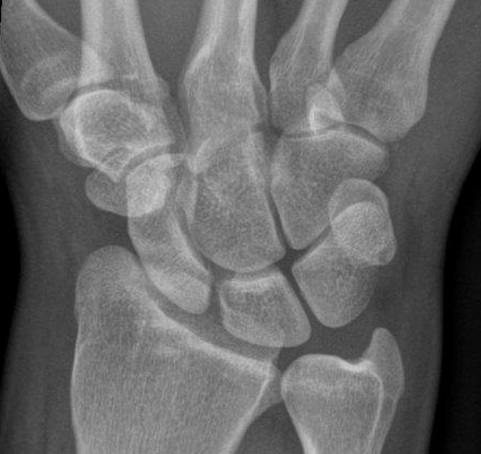

30yo who fell awkwardly. Which carpal bone has he dislocated? Gepost op 13 september 2017 door netwerkvsseh Which carpal bone has he dislocated? @radiopaedia.org Dit delen: Delen op X (Opent in een nieuw venster) X Share op Facebook (Opent in een nieuw venster) Facebook Delen op LinkedIn (Opent in een nieuw venster) LinkedIn E-mail een link naar een vriend (Opent in een nieuw venster) E-mail Afdrukken (Opent in een nieuw venster) Print Vind-ik-leuk Aan het laden... Gerelateerd